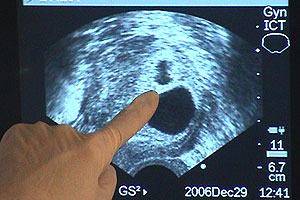

For most people adding to a family is a wonderful time, but for Anna it's been filled with anguish.